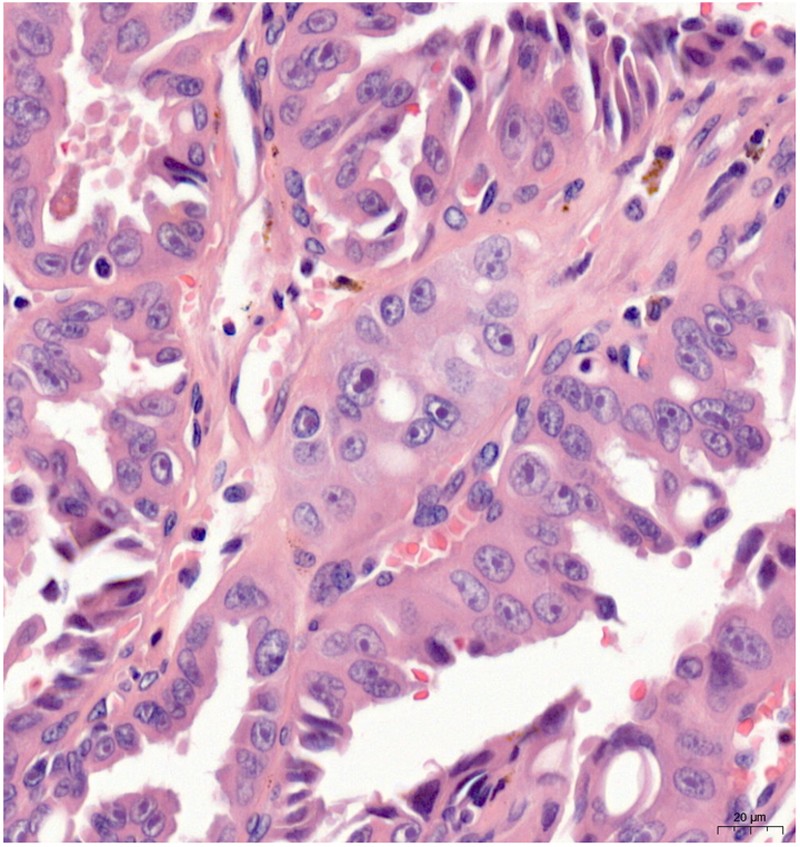

Fig. 1

Hereditary leiomyomatosis and renal cell carcinoma tumor cells had a very prominent eosinophilic nucleus with a large nucleolus and perinucleolar halo at high magnification (hematoxylin and eosin)